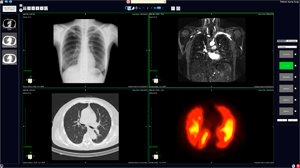

また,VirtualPlaceの画像処理技術の新開発や高度化が進んでいる。なかでも,心臓解析機能は大幅に改良され,表示方法の改善,追従精度の向上などが図られるとともに,フルオート解析(Aze Auto Analyzer:AAA)を実装し,画像の転送から処理・表示に至るまでの完全自動化が実現した。ほかにも,T1/T2マッピング,肺結節の自動抽出機能,血管解析機能などが新しく追加されている。

![]() 肺結節の自動抽出機能 |

![]() 血管解析機能 |